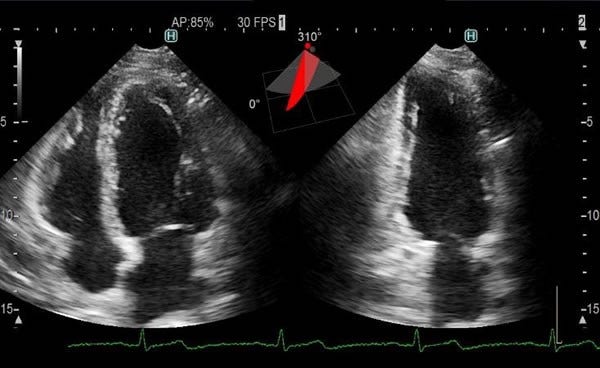

[画像]3D経胸壁マトリックスプローブによる心臓の2断面同時表示 3D経胸壁マトリックスプローブによる心臓の2断面同時表示

胸にプローブを当てて心臓の検査をする経胸壁エコー検査では、拡張・収縮を繰り返す心臓の断面の画像を見ることにより、心臓の血液ポンプとしての機能にどのような問題があるかを診断します。

従来のプローブは一度に一断面だけを表示するため、心腔(心房・心室)の容積を測るには、検査者が必要な断面ごとにプローブを手で動かして画像を取り込む必要がありました。新開発の3D経胸壁マトリックスプローブは、検査者がプローブを動かさずに必要な断面全てを一心拍の間に取り込むことが可能です。